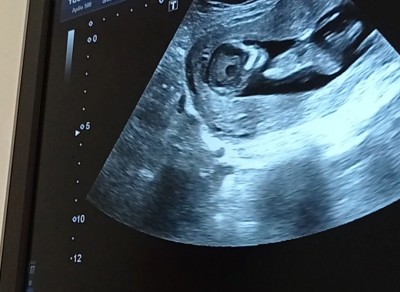

hanimlar sizce cinsiyeti nedir anlayan varsa yorum yapabilir mi

Gebelik haftası 12+2

Erkeğe benziyo canım hayırlı olsun tosuncuğun tabiii eğer yanılmıyorsam:angel:

Doktor bi kız diyo bi erkek yani emin olamiyor şuan 30+5 günlük nerdeyse doğuracam artık doğduğun da belli olur ama ben hep erkek hissediyorum

Doktorun ultrasonu gayet güzel göstermiş bacak arası görünmedi mi